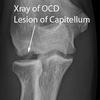

Panner disease

Osteochondrosis of capitellum